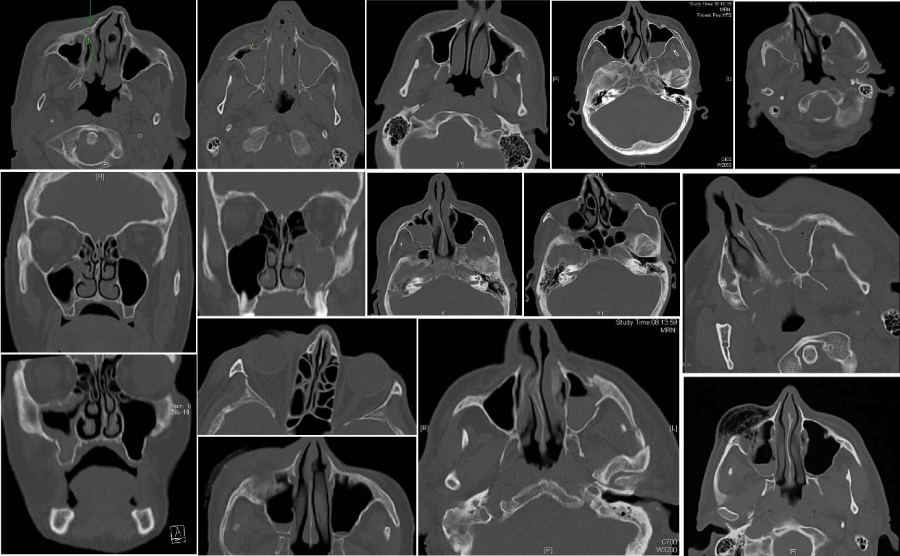

Figure 3:

Samples of study-CAT-scans of patients aged 70+ showing above critical-size-defect dislocations of isolated zygoma-tripod and/or arch-fractures and related fractures of the orbital-floor.

a) Fractures with no or minimal dislocation (max. 1 - 2,7 mm) and no fracture-stages/fracture-crepitations/maxillary mobility palpable in clinical investigation (Figure 2)

b) Fractures with dislocations above critical-size-defects (2,7mm [17Udagawa A, Sato S, Hasuike A, Kishida M, Arai Y, et al. (2013) Micro CT observation of angiogenesis in bone regeneration. Clin Oral Implants Res 24: 787-792.]) and/or fracture-stages/fracture-crepitations/maxillary mobility palpable in clinical investigation (Figure 3)

Although CAT-Scan diagnosis and 3D-reconstructions (Figures 3, 4 and 6) are valuable tools to determine the precise fracture -pattern, number of and distance between fracture-fragments and volume of intraorbital emphysema, they cannot replace a thorough clinical investigation by palpation and functional analysis of the eye-bulbs and stomathognathic system which has to take place firsthand.